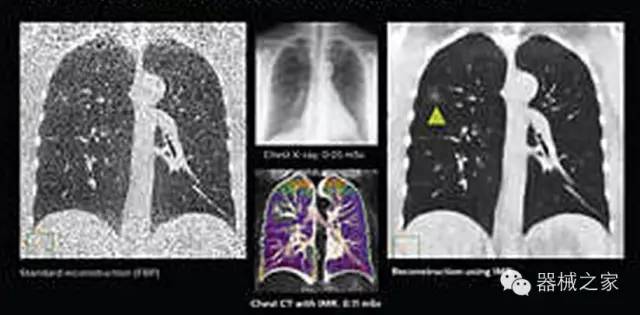

1.低劑量下的胸部顯影

IQon光譜CT能夠按照需求提供光譜量化和工具,并能通過簡單工作流程、在低劑量下對結(jié)構(gòu)進行定性分析

IQon光譜CT -- 是業(yè)界首臺以探測器為成像基礎(chǔ)的光譜CT,它可以在單次常規(guī)掃描下獲得傳統(tǒng)解剖影像及光譜功能影像。不僅可以提供精準的診斷信息,還可簡化工作流程、在低劑量下完成定量與定性分析。